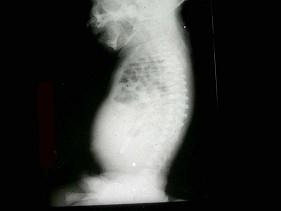

问题 男,15天,进食呕吐5天、呼吸困难2天,如图所示,最可能的诊断为?(?)

选项 A.先天性肺气肿 B.左侧膈疝 C.右位心 D.右侧肺不张 E.右肺发育不全

答案 B